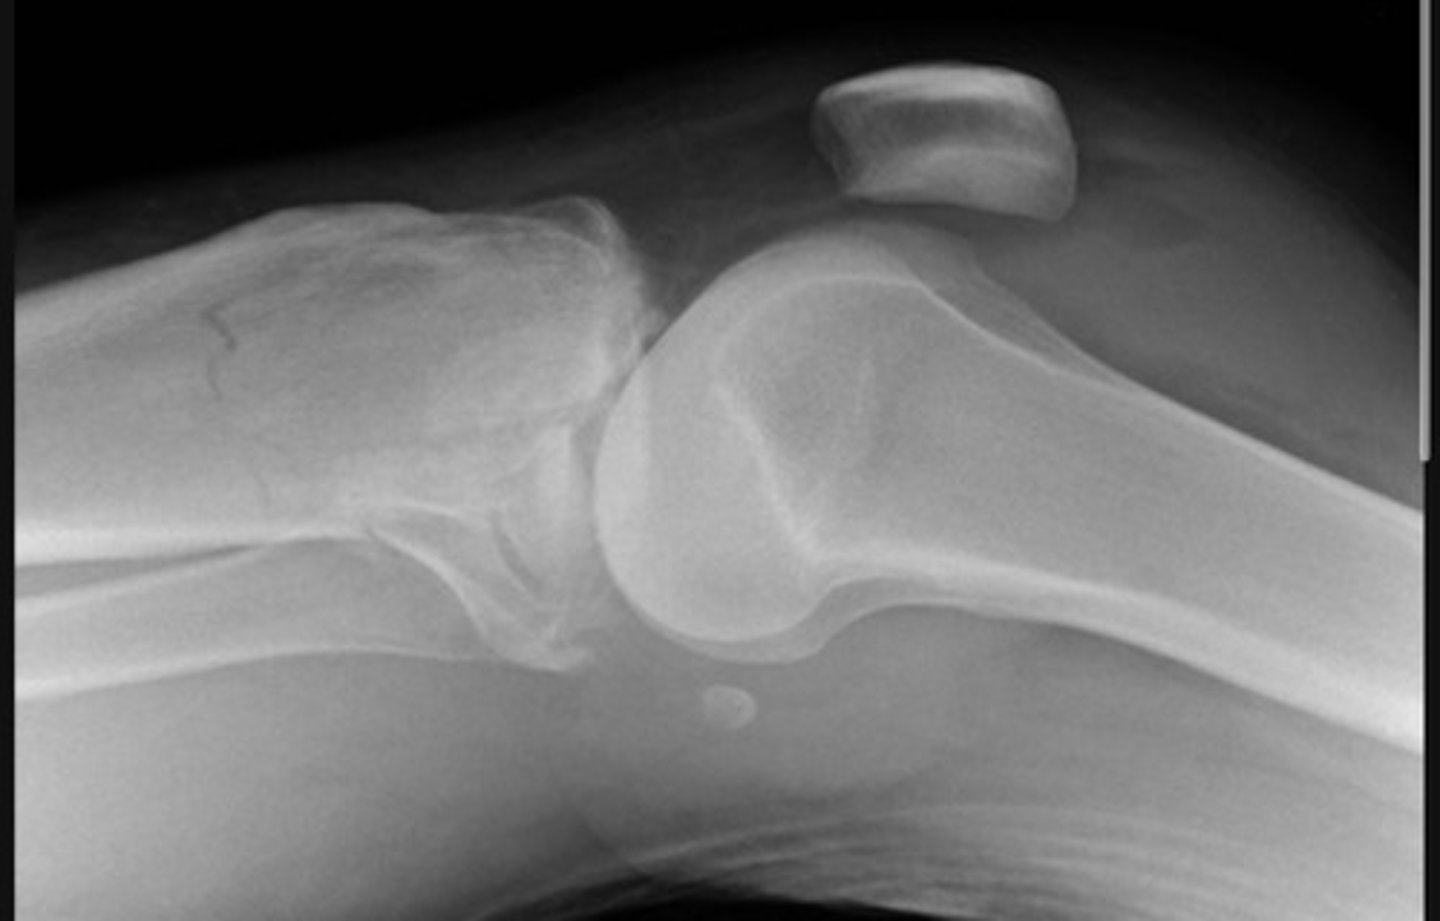

severely comminuted fracture of the tibial plateau and a lipohaemarthrosis

Lateral patella dislocation